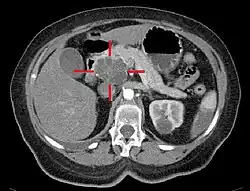

Medical imaging techniques, such as computed tomography (CT scan) and endoscopic ultrasound (EUS) are used both to confirm the diagnosis and to help decide whether the tumor can be surgically removed (its "resectability").[12] On contrast CT scan, pancreatic cancer typically shows a gradually increasing radiocontrast uptake, rather than a fast washout as seen in a normal pancreas or a delayed washout as seen in chronic pancreatitis.[58] Magnetic resonance imaging and positron emission tomography may also be used,[2] and magnetic resonance cholangiopancreatography may be useful in some cases.[34] Abdominal ultrasound is less sensitive and will miss small tumors, but can identify cancers that have spread to the liver and build-up of fluid in the peritoneal cavity (ascites).[12] It may be used for a quick and cheap first examination before other techniques.[59]

.jpg)